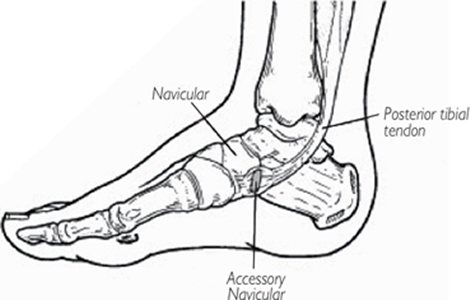

주상골(navicular bone)은 발목뼈(족근골)(tarsal bone)를 구성하는 뼈(bone) 중 하나입니다. 위치상으로 살펴봤을 때 입방골(cuboid bone)과 설상골(cuneiform bone), 그리고 거골(talus) 사이에 자리 잡은 뼈(bone)입니다. 그렇다 보니 방향적인 위치상 발목 안쪽(internal ankle)으로부터 타고 내려와, 실질적으로 발의 아치(foot arch)가 가장 높게 실리게 되는 위치상에 존재하게 됩니다. 주상골(navicular bone)의 자세한 모습과 위치는 사진을 통해서 제대로 살펴볼 수 있습니다.

사진에서 살펴본 것과 같이 주상골(navicular bone)은 단일한 뼈(bone)입니다. 하지만 부주상골증후군(accessory navicular syndrome)은 주상골(navicular bone)이 하나가 아닌 증상과도 같습니다. 그래서 그 이외의 뼈(bone)를 부주상골(accessory navicular bone)이라 부릅니다. 기본적으로 부주상골(accessory navicular bone)은 더 작은 크기(small size)로 형성되어있으며, 그 위치는 부주상골(accessory navicular bone)이라는 이름답게 주상골(navicular bone) 옆(lateral)에 자리 잡게 됩니다.

발과 발목(foot & ankle)은 쉽게 손상(injury)을 받은 신체 부위 중 하나입니다. 이것은 아무래도 가장 많은 체중(body weight)이 실기는 지점이기도 하거니와, 우리가 생각하지 못할 정도로 보행 움직임(gait movement)만 보더라도 연속적이고 복합적인 다관절 및 다근육 움직임(movement of multi joint & multi muscle)이 발생되기 때문입니다. 그러니 발과 발목 손상(foot & ankle injury)은 해당 지점에서 결함 가능한 조직(defect tissue)들은 무수히 많으며, 그 과정에서 주상골(navicular bone)이 골절(fracture)되거나, 혹은 애초에 부주상골(accessory navicular bone)이 존재하고 있던 상태에서 인접 조직(adjacent)들의 경로 변화(pathway chane), 이탈(breakway), 끼임 등의 원인으로 부주상골(accessory navicular bone)과 조직(tissue)들 사이에서의 마찰(friction)이 증가될 수 있습니다. 특히나 발과 발목(foot & ankle)을 동시에 경유하고 있는 일부 근육(muscle)들이, 부주상골(accessory navicular bone)과 주상골(navicular bone) 바로 옆을 지나가기 때문에 이곳에서 (손상 이후 또는 드물게 선천적인 결함(innate defect)에 의해) 강한 마찰(friction)이 지속적으로 불필요하게 가해진다면, 이와 같은 상황에서는 제거의 대상이 되기도 합니다. 하지만 이러한 필요성 또한, 본 포스팅에서 사전에 나열했던 사항들을 기반으로 하여 고려해야 할 것입니다.